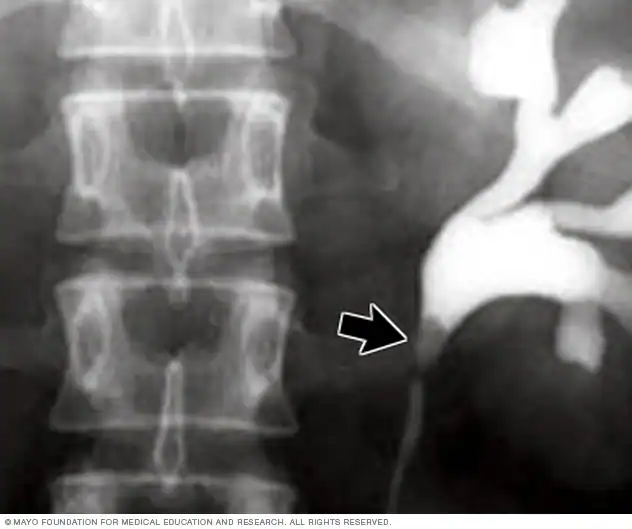

تصویر اشعه ایکس از سنگ کلیه

این تصویر با استفاده از ماده حاجب سنگ کلیهای را نشان میدهد که در محل اتصال کلیه به حالب قرار گرفته است.